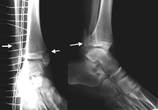

1 2 3 4

Рис..15. 1 – виды секвестров; 2 – острый остеомиелит|; 3 – хронический остеомиелит|; 4 – огнестрельный остеомиелит|.